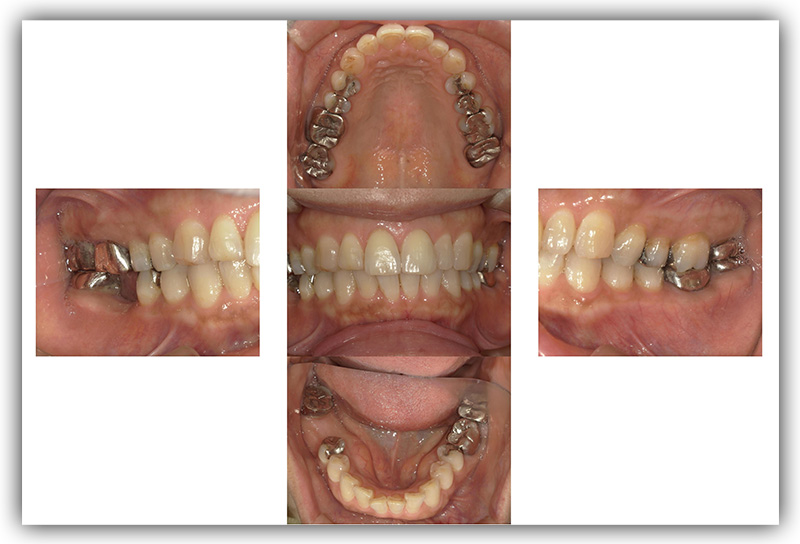

CASE_02

60代男性(インプラント)

- 患者さん情報(年齢・性別)

- 60代 男性

- 主訴

- 被せものが外れたところをインプラントにしたい

- 治療箇所

- 2箇所

- 治療方法

- インプラント

- 費用

- 約86万円

- 治療期間

- 約半年

- その治療によるリスク・副作用

-

- 治療期間がながい、外科的治療が必要